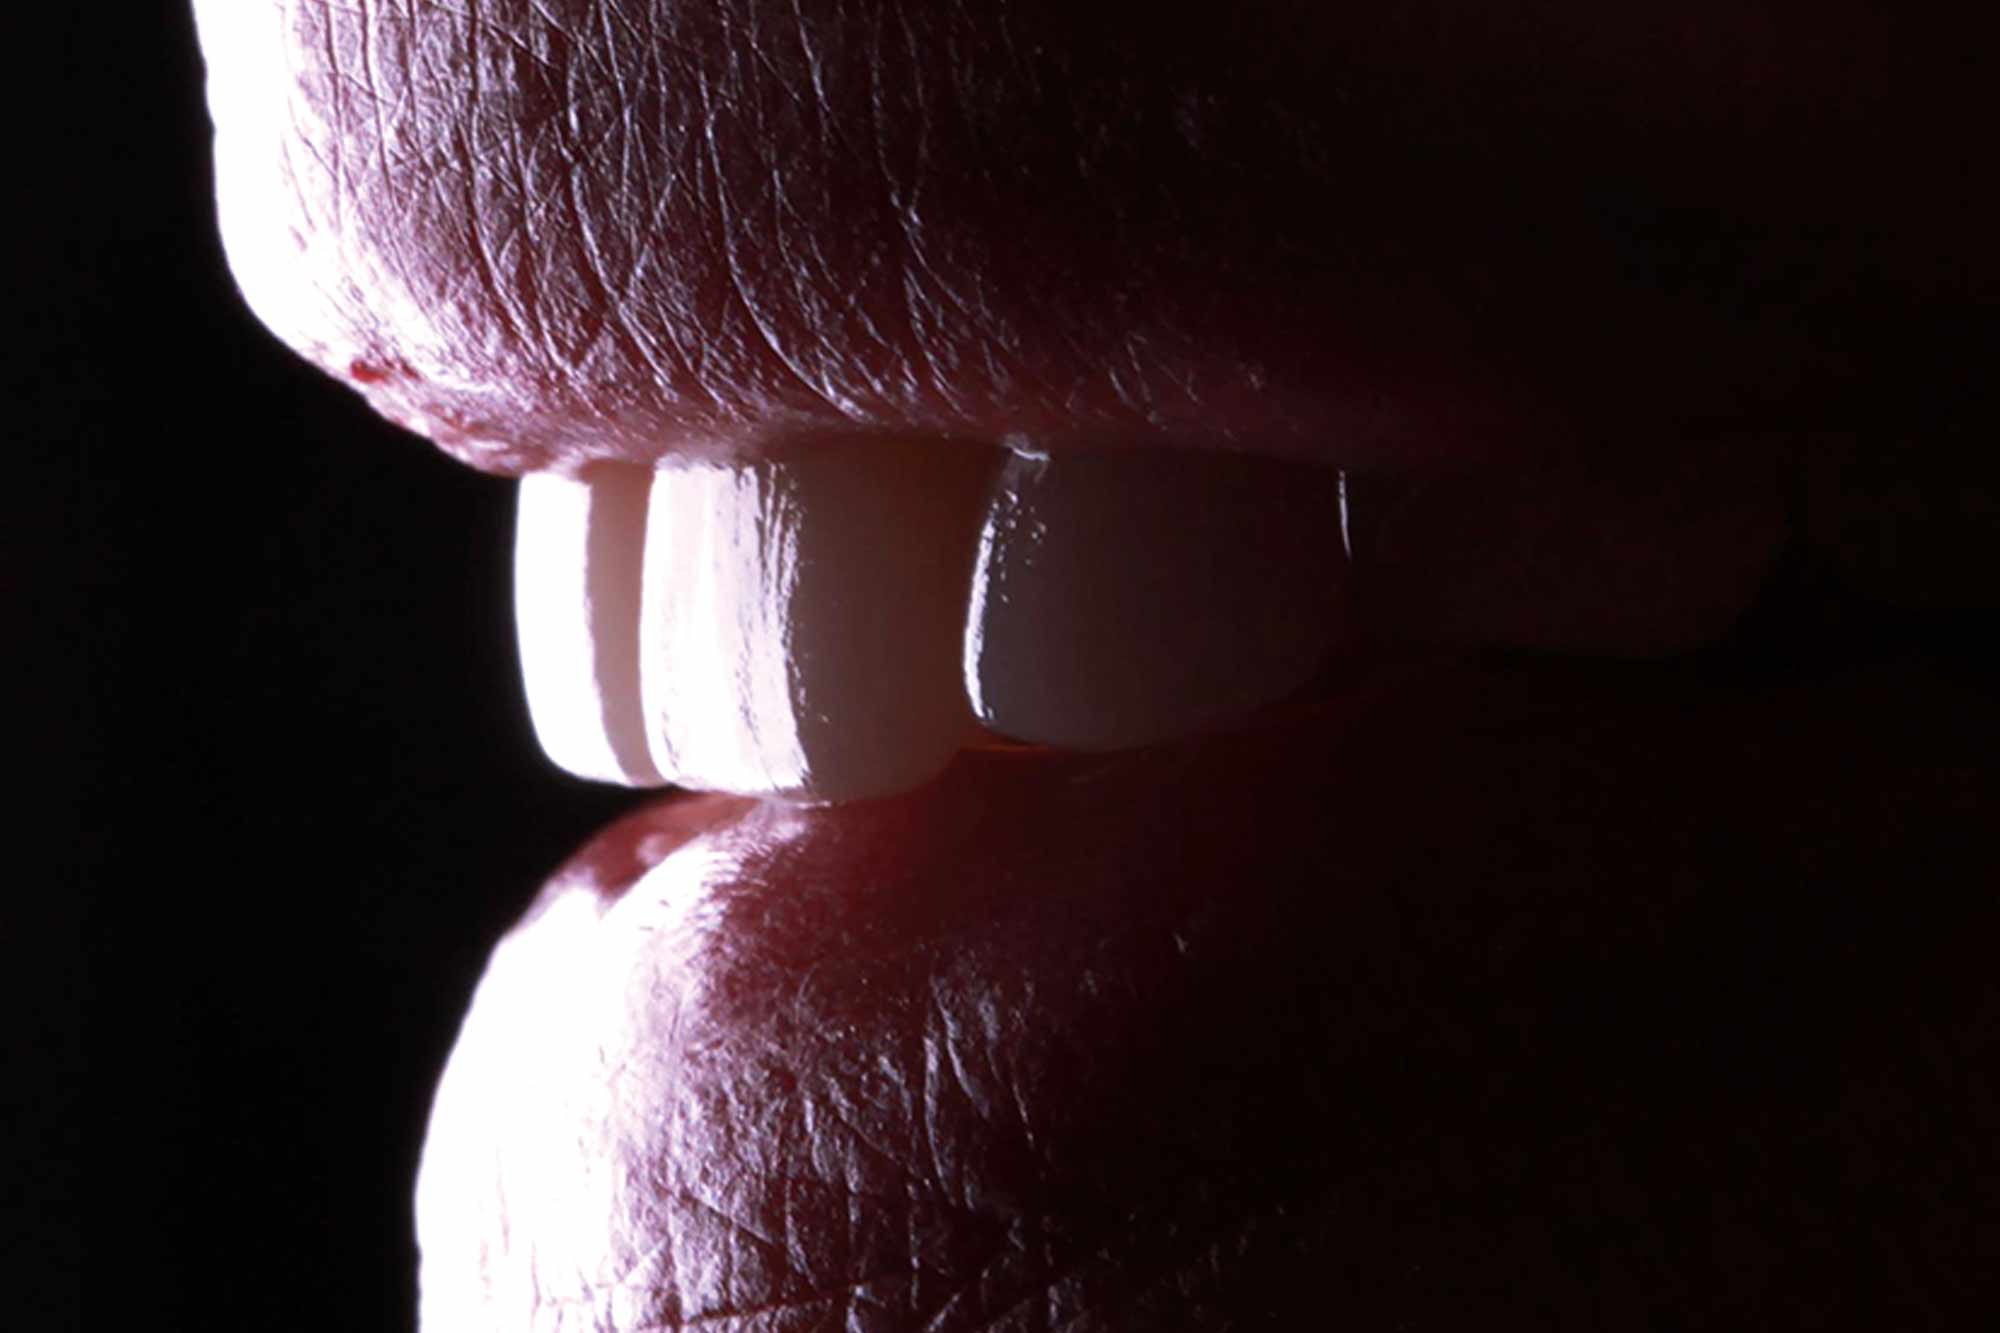

The mock-up was placed in mouth and the patient had the chance of contemplating the provisional smile with great joy (Figure 6).

After less than three hours, they were ready to be fitted and, prior to cementing them, the patient was given the opportunity to contemplate them using a mirror and she couldn’t stop smiling.

The cementing of the four lithium disilicate crowns was performed using Relyx dual-cure cement, with a careful excess removal and adequate polishing (Figures 8 to 10).